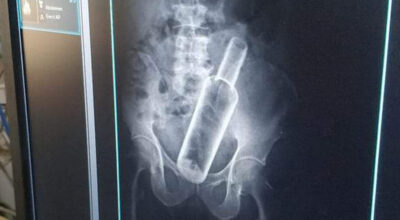

धनगढीमा वृद्धको पेटमा बोतल भेटियो

काठमाडौं, चैत ३० । सेती प्रादेशिक अस्पतालमा उपचार गर्न गएका एक वृद्धको पेटमा बोतल भेटिएको